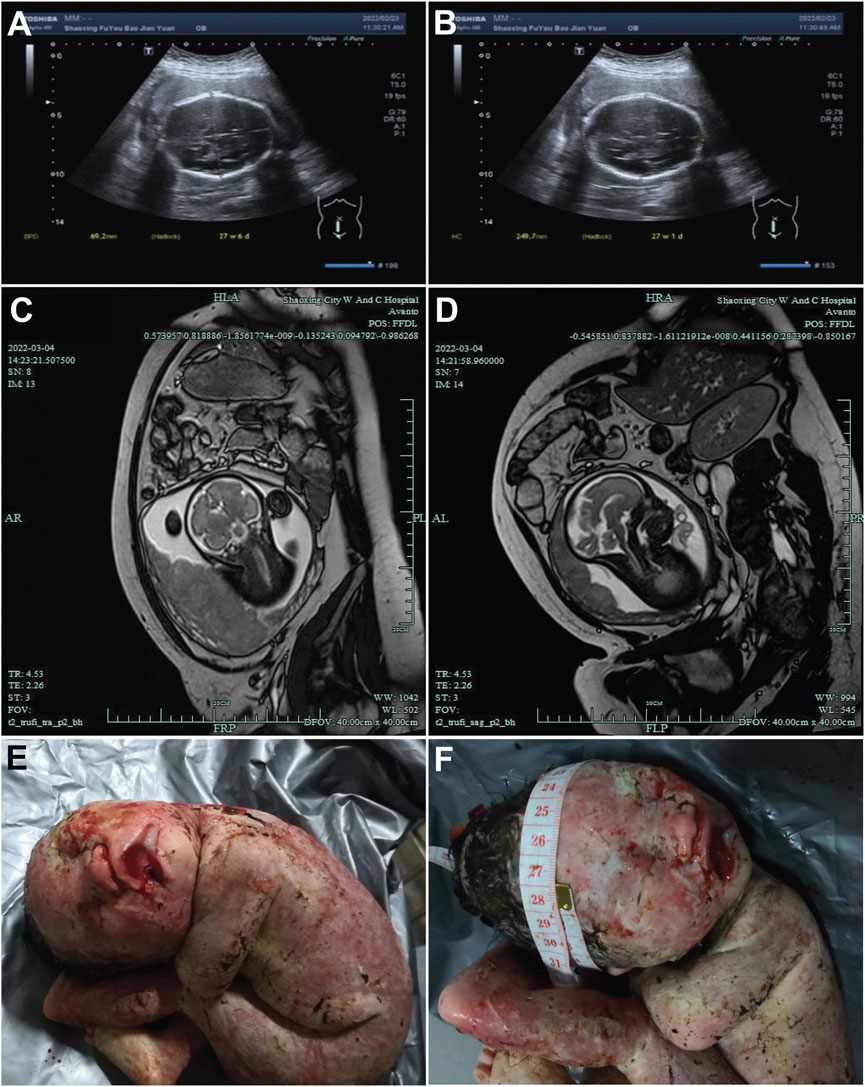

The proband’s mother was a 30-year-old Chinese Han woman with regular 30-day menstrual cycles and no significant medical history. Her pregnancy was confirmed after 30 days of amenorrhea with a positive urine test. She received standard prenatal care, including 0.4 mg/day folic acid supplementation during the first trimester, with normal oral glucose tolerance test results and no exposure to teratogens. Initial prenatal screening at 13+1 weeks showed a normal nuchal translucency measurement (2.8 mm) and low-risk non-invasive prenatal testing results. However, subsequent ultrasounds revealed progressively severe fetal growth abnormalities, with head circumference measurements declining to the 0.1st percentile by 24+2 weeks and estimated fetal weight below the 1st percentile (Figures 1A,B). Fetal MRI at 30+6 weeks confirmed significant microcephaly (head circumference 266 mm, equivalent to 28 weeks’ gestation) (Figures 1C,D). Following a multidisciplinary evaluation at 31+5 weeks that confirmed severe fetal growth restriction with microcephaly, the parents elected to terminate the pregnancy after ethical committee approval. The male fetus was delivered stillborn without apparent dysmorphic features. Postmortem genetic testing was performed to determine the etiology of these findings, with the aim of guiding future pregnancies. The parents had no family history of genetic disorders or previous adverse pregnancy outcomes.

FIGURE 1

Ultrasound and magnetic resonance images of the fetal head. (A,B) Ultrasound images of the fetal head at 27 weeks + 4 days of gestation, showing the fetal head from different sections. The measured values indicated in the figures (such as 46.2 mm and 240.7 mm) represent the relevant diameters of the fetal head in the corresponding sections. (C,D) MRI images of the fetal head at 27 weeks +4 days of gestation, presenting the structure of the fetal head from different angles. (E,F) Post-induction labor photographs of the fetus. E presents the general appearance of the fetus. F focuses on the fetal head, where a measuring tape is used to document the head circumference.